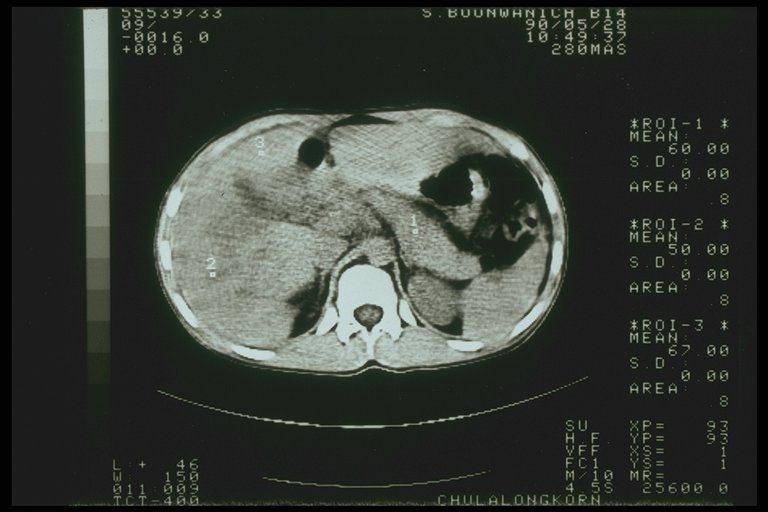

Severe liver injury with intrahepatic hematoma

Severe liver injury, multiple laceration over the right lobe are noted from CT scan